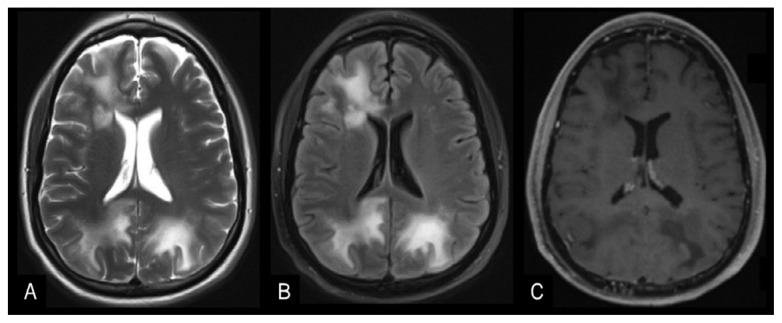

Tophaceous Gout in the Axial Skeleton: An Unusual Case with Key Imaging Characteristics.